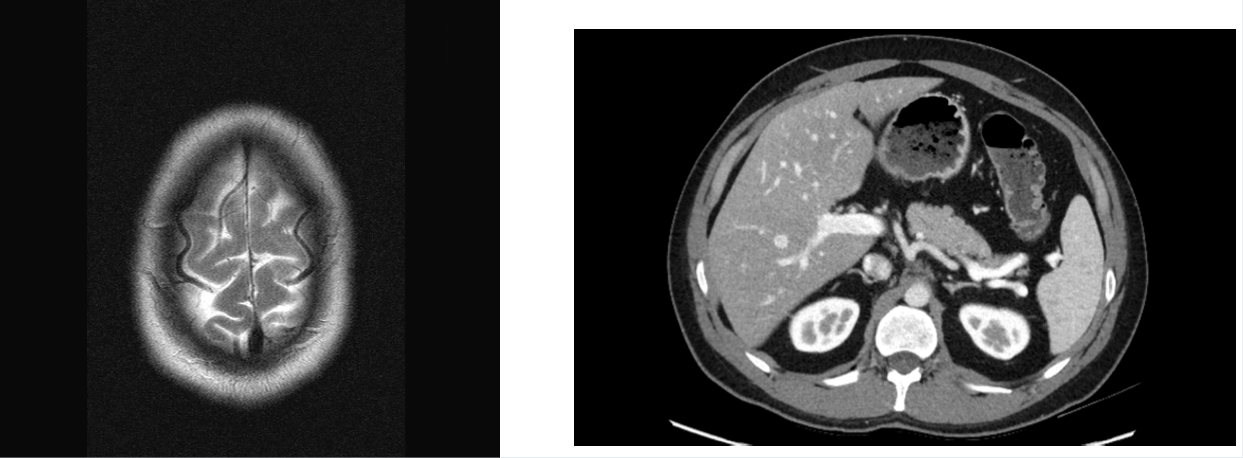

Axial CT images

Presented as if the viewer is standing at the foot of the patient’s bed; the patient’s right is to the viewer’s left; the anterior aspect of the patient is toward the top of the image